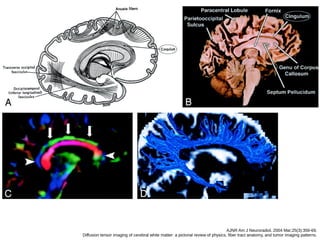

Fibras de associação

● Cíngulo

● Fascículo occipitofrontal superior / inferior

● Fascículo uncinado

● Fascículo longitudinal superior / arqueado

● Fascículo longitudinal inferior (occipitotemporal)

● Começa na área cortical paraolfatória do

córtex abaixo do rostro do corpo caloso, segue

o giro do cíngulo, seguindo para o giro

parahipocampal e uncus.

● Conecta porções do lobo frontal, pareital e

temporal.

CÍNGULO

AJNR Am J Neuroradiol. 2004 Mar;25(3):356-69.

Diffusion tensor imaging of cerebral white matter: a pictorial review of physics, fiber tract anatomy, and tumor imaging patterns.

A, cíngulo

B, fascículo occipitofrontal inferior e longitudinal inferior.